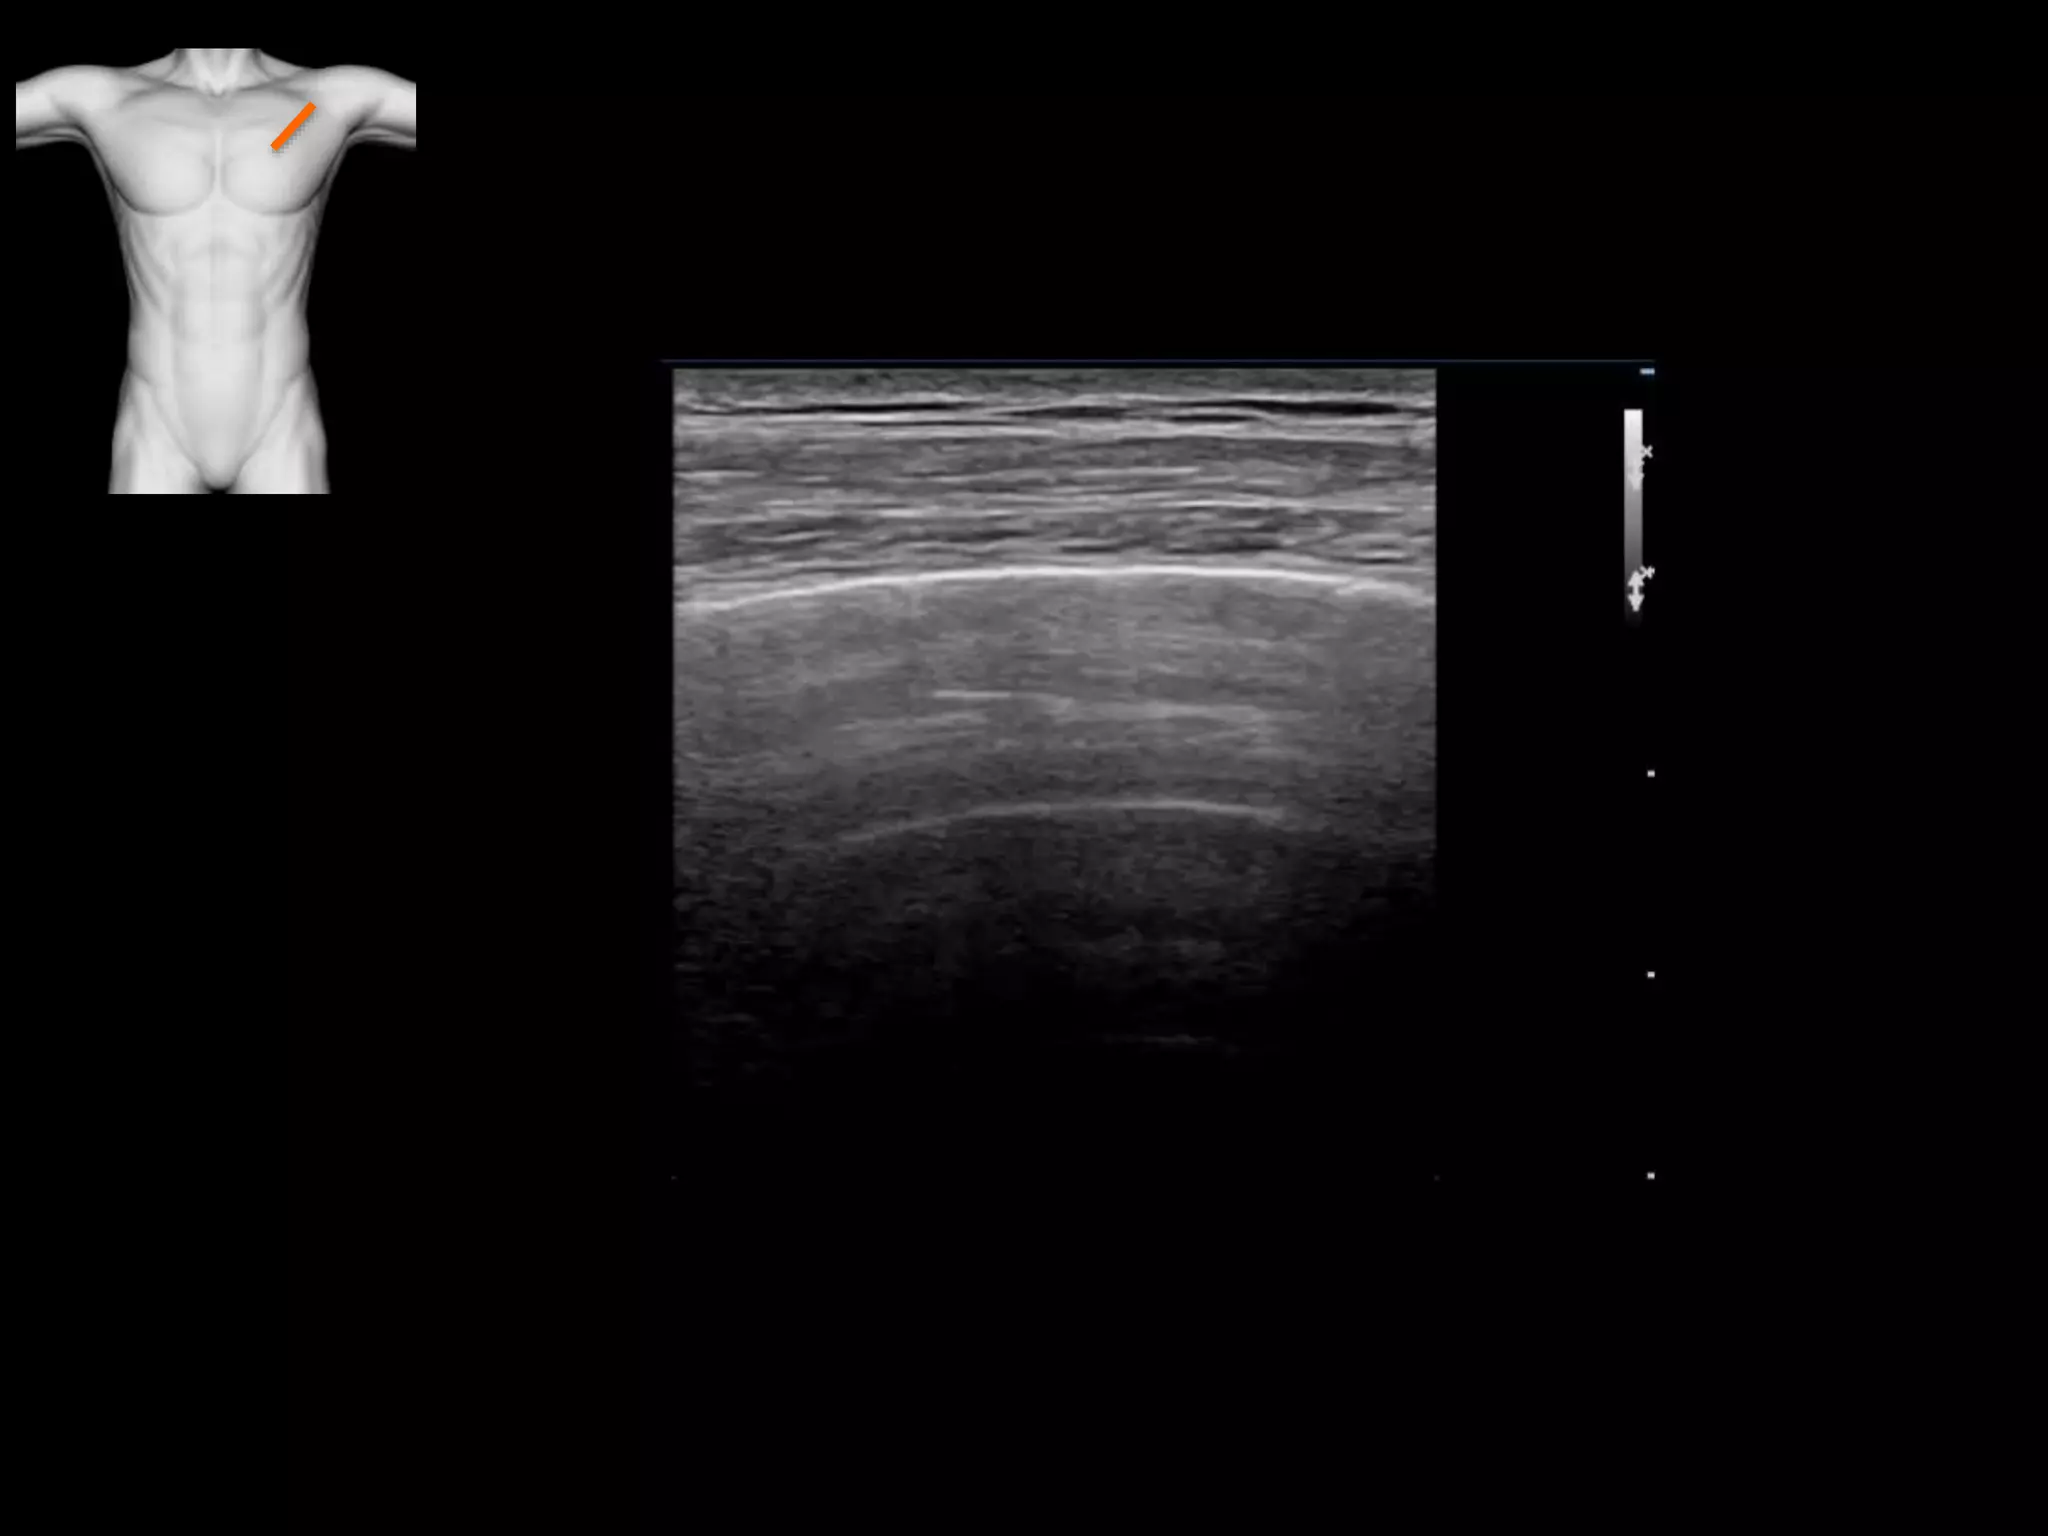

Normal lung and pleura

Pulmonary oedema

The B-Line

B-lines – pulmonary oedema, pneumonitis, contusion,

early pneumonia, fibrosis, deep to other pathology